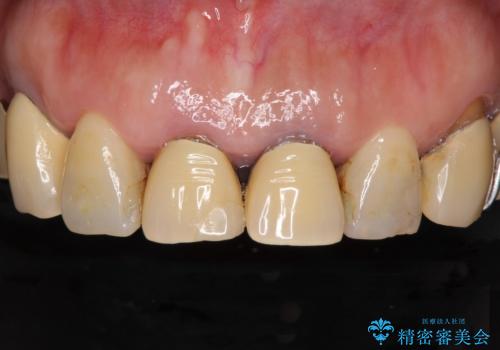

[MTMを行い歯の神経を保存] 歯周補綴ブリッジ

![[MTMを行い歯の神経を保存] 歯周補綴ブリッジの症例 治療前](https://seimitsushinbi.jp/wp/wp-content/uploads/2021/04/21310c2f37874ac2f2ba9939da2fee68-500x350.jpg?v=1618452125)